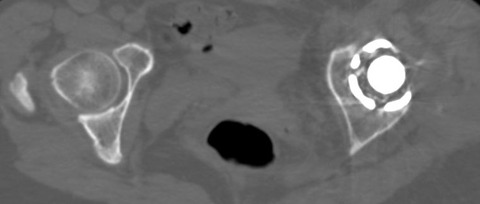

しかし、術前CTで寛骨臼の前方開角が45度、大腿骨頚部前捻角が40度でした...。大腿骨頚部前捻角はまだしも、寛骨臼前方開角は看過できません。

このままの角度でカップを設置すると前方脱臼する可能性があります。しかし、前方開角を減じるとカップ前方で腸腰筋との Irritationを併発して股関節痛を残す原因となりそうです。

かなり検討したのですが、結局カップの前方開角度は通常の症例と同様に20度に減捻して、腸腰筋の Irritationにはある程度目をつぶることしました。

大腿骨にも過大前捻があり、関節不安定性がどうなるのか予測できなかったため、S-ROM-Aでこちらも20度減捻しました。